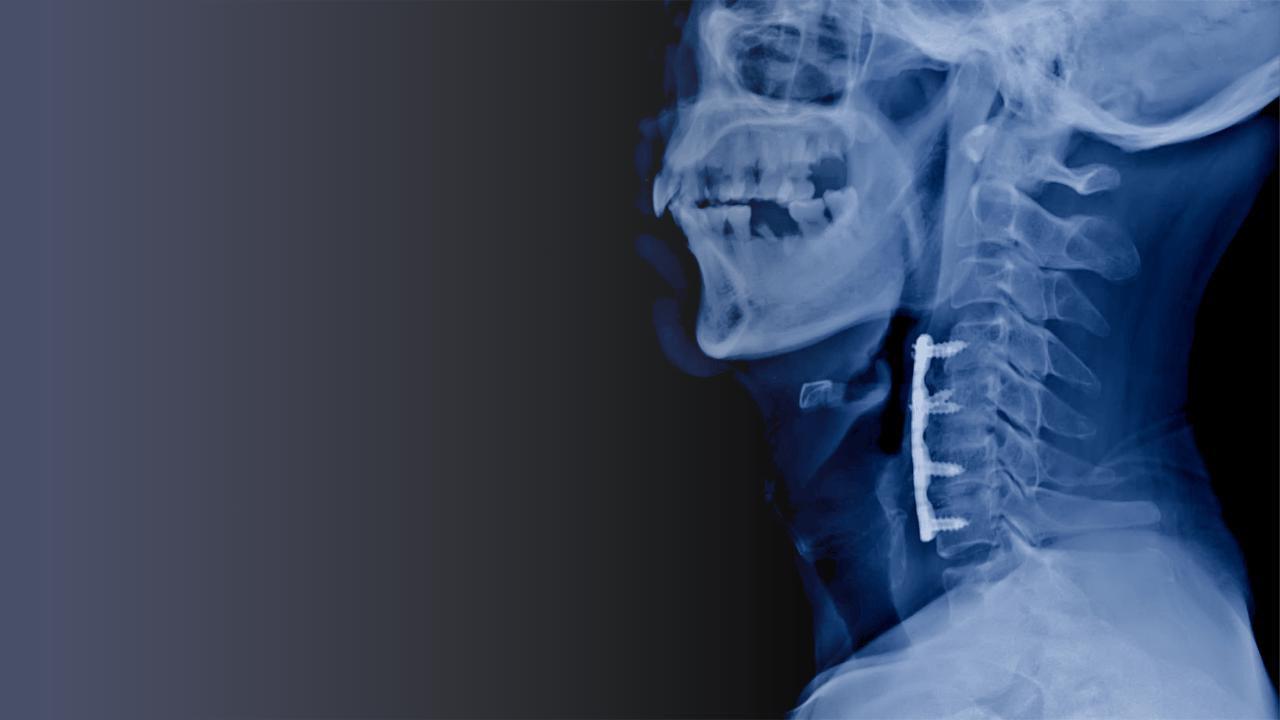

Cervical spinal fusion is a serious intervention—typically reserved for cases involving instability, myelopathy, or structural deformity. But what about the countless individuals living with chronic neck pain who don’t meet surgical criteria? For them, medical massage offers a conservative, evidence-informed alternative that targets the muscular, fascial, and neurological contributors to pain.

4. Post-op recovery to protect adjacent segments